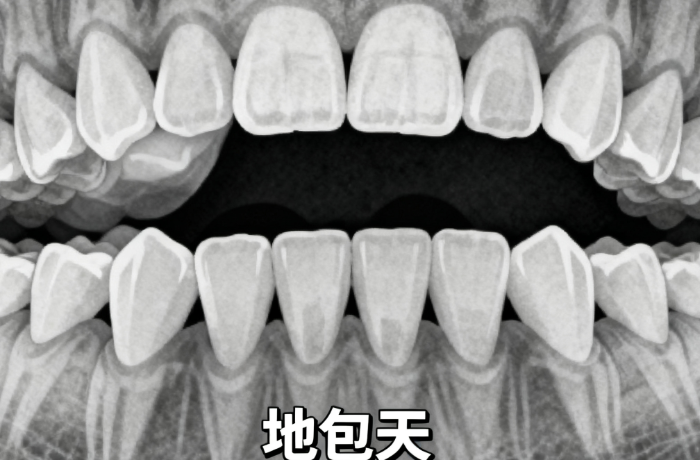

齙牙真的太影響樣貌和自信了,笑不敢露齒,拍照總愛側(cè)臉。palmspringsgreathomes.com糾結(jié)半年后,我在牙博士做了傳統(tǒng)金屬矯正,12000元起的價(jià)格,力度大成效明顯。這篇把全過程、價(jià)格、避坑全說清,給想矯正的姐妹們實(shí)打?qū)嵉膮⒖肌?/p>